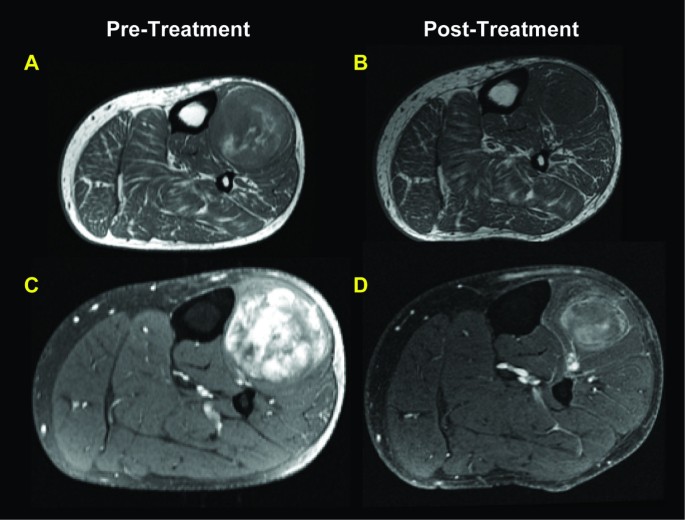

MRI revealed a decrease in tumor area in all but one tumor (median decrease in size was 65%). A decrease in contrast enhancement was found in most tumors (n = 5,>50%; n = 9, 25-49%; n = 7, <25%) (Figure4), histologically corresponding to increased hyalinization, decreased cellularity and decreased vasculature. Seven tumors developed an increase in a register characteristic of mature adipose tissue (n = 2,>50%; n = 2, 25-49%; n = 3,<25%) (Figure5). Four of 6 tumors with histological adipocytic maturation >50% also had increased adipose signal detected by MRI (>25%).

Example of MRI findings seen in the majority of myxoid liposarcomas undergoing treatment in our series. T1 weighted axial image of the calf with mass (A) pre-treatment and (B) post treatment showing a reduction in tumor size and decreased adipocytic content. T1 weighted post contrast media with fat saturation with (C) pre-treatment demonstrating an extensive heterogeneous enhancement, while (D) post treatment shows decreased tumor size and decreased enhancement greater than 50%. These findings correspond to increased hyalinization and decreased vascularity histologically.